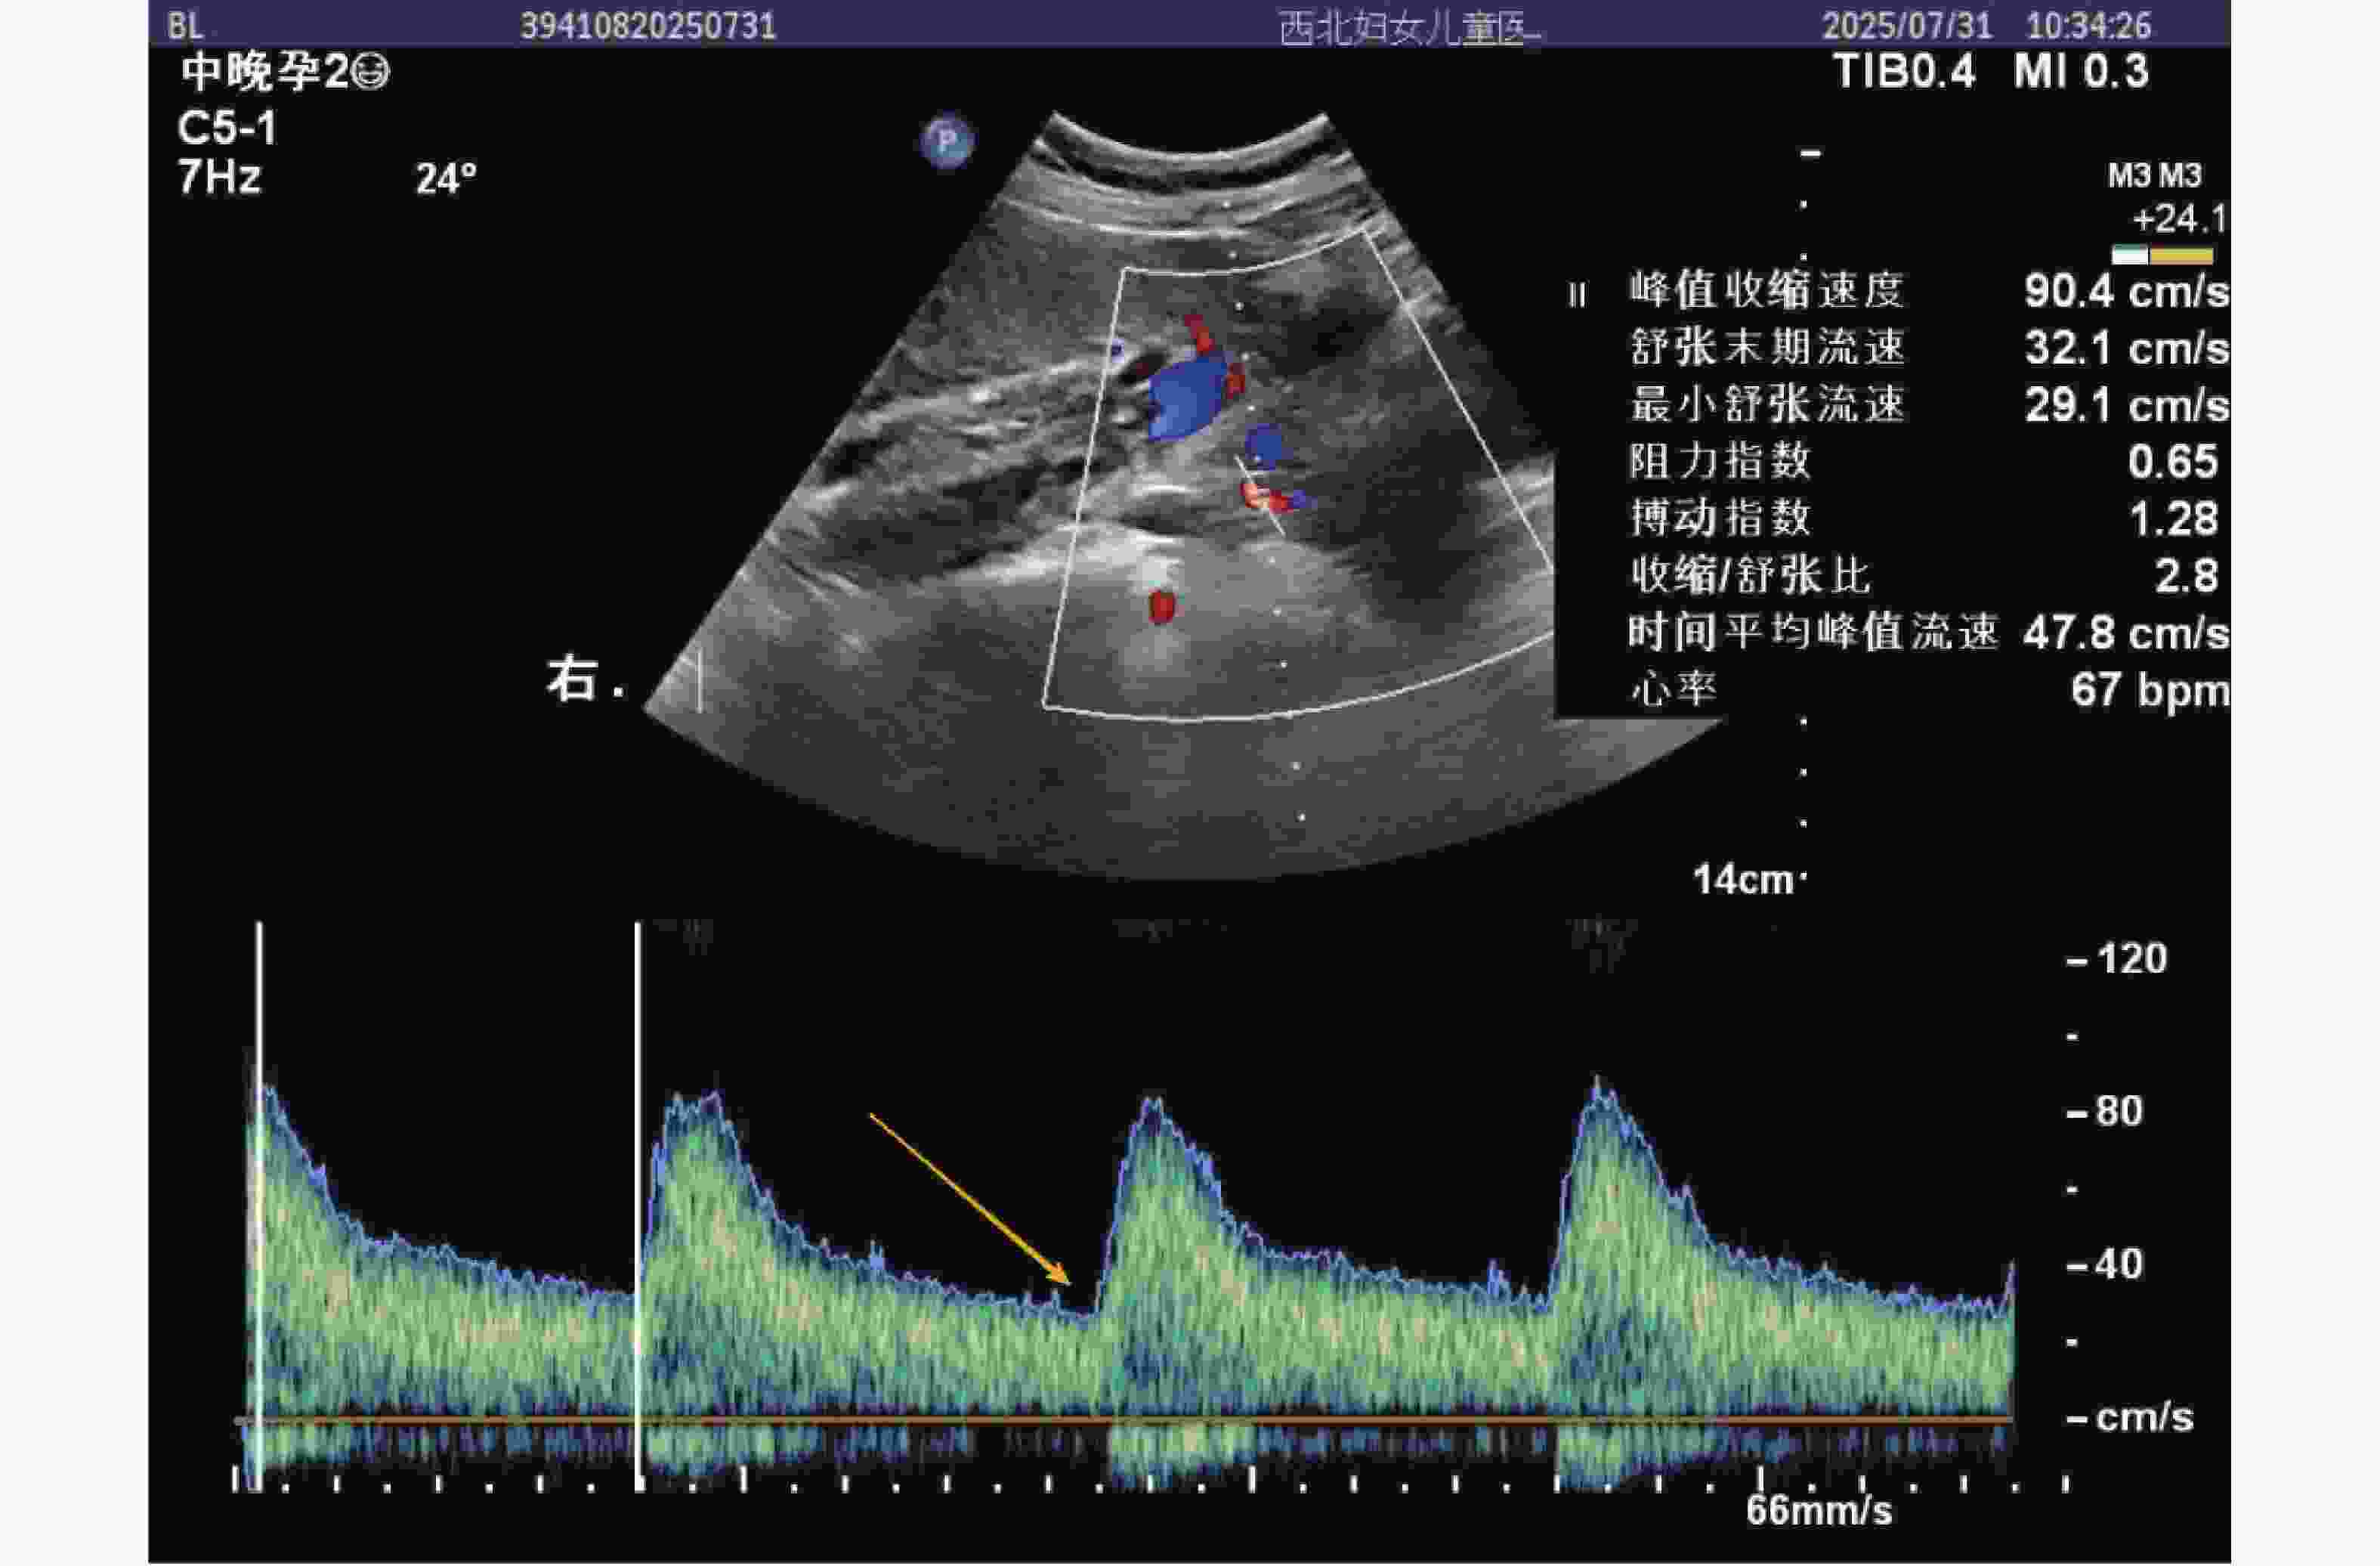

图  2  正常组(健康常规检查孕中期孕妇)子宫动脉血流频谱图

注:图中红色圆点标注 PI(1.28)、RI(0.65)、S/D(2.8)测量点,黄色箭头指示舒张期流速平稳段(无切迹),峰值收缩速度 90.4 cm/s,舒张末期流速 32.1 cm/s,血流阻力较低,符合正常孕中期子宫动脉血流特征,时间平均峰值流速 47.8 cm/s,提示胎盘灌注充足。

Figure  2.  shows the uterine artery blood flow spectrum of the normal group (pregnant women in the second trimester of pregnancy undergoing routine health check-ups)